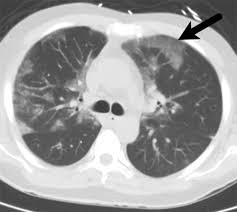

Such cancers can be misdiagnosed as inflammatory lung diseases, delaying accurate diagnosis. Recurrent lung infections, such as bronchitis or pneumonia. It is quite less likely that people confuse merkel cell carcinoma and melanoma with psoriasis. There are some risk factors of lung cancer, and smoking is the leading risk factor. Organising pneumonia (op) is a distinct clinicopathological entity resulting from pulmonary reaction to noxious environmental or endogenous factors, but also idiopathic cases have been noted.

Pneumonia Linked To Lung Cancer Risk from europeanlung.org Pneumonia and lung cancer both occur in the lungs and share several overlapping symptoms. Pneumonia is an inflammatory process of one or two lungs, which is characterized by a rise in temperature, the release of fluid into the alveoli. Pneumonia has a number of potential causes, including infection, toxic inhalation and allergic reaction childhood pneumonia may also be mistaken for appendicitis. Frequently, small foci of op accompany lung cancer infiltrations. The lungcancer.net team does not recommend or endorse any products or treatments discussed herein. Can skin cancer be mistaken for psoriasis? If a person has lung cancer and gets pneumonia, the prognosis and life expectancy is can secondhand smoke cause lung cancer? Acute pneumonias, acute viral respiratory infection.

Ct Findings Of Covid 19 Pneumonia And Mimicking Diseases In Patients With Lung Cancer Iaslc from www.iaslc.org A tumor site located in the lung tissue or subpleural: Can pneumonia cause this cancer, too? Lung cancer and pneumonia have similar symptoms, and both can be fatal. If you quit smoking, even after smoking for many years. It is most commonly caused by aspiration of oral secretions by patients who have impaired consciousness. Lung cancer, also known as lung carcinoma, is a malignant lung tumor characterized by uncontrolled cell growth in tissues of the lung. Symptoms are persistent cough, fever, sweats, and weight loss. A person with lung cancer can get pneumonia more easily because their lungs.